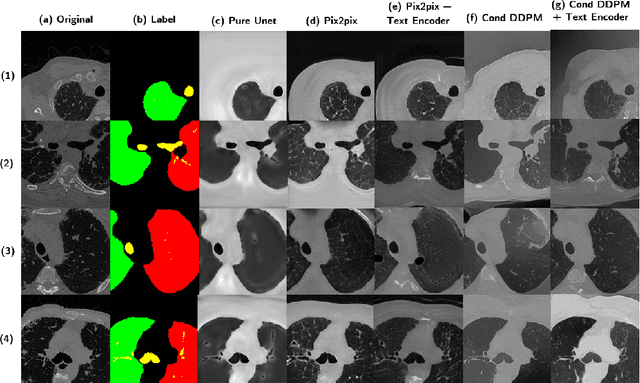

Abstract:Deep generative models have significantly advanced medical imaging analysis by enhancing dataset size and quality. Beyond mere data augmentation, our research in this paper highlights an additional, significant capacity of deep generative models: their ability to reveal and demonstrate patterns in medical images. We employ a generative structure with hybrid conditions, combining clinical data and segmentation masks to guide the image synthesis process. Furthermore, we innovatively transformed the tabular clinical data into textual descriptions. This approach simplifies the handling of missing values and also enables us to leverage large pre-trained vision-language models that investigate the relations between independent clinical entries and comprehend general terms, such as gender and smoking status. Our approach differs from and presents a more challenging task than traditional medical report-guided synthesis due to the less visual correlation of our clinical information with the images. To overcome this, we introduce a text-visual embedding mechanism that strengthens the conditions, ensuring the network effectively utilizes the provided information. Our pipeline is generalizable to both GAN-based and diffusion models. Experiments on chest CT, particularly focusing on the smoking status, demonstrated a consistent intensity shift in the lungs which is in agreement with clinical observations, indicating the effectiveness of our method in capturing and visualizing the impact of specific attributes on medical image patterns. Our methods offer a new avenue for the early detection and precise visualization of complex clinical conditions with deep generative models. All codes are https://github.com/junzhin/DGM-VLC.